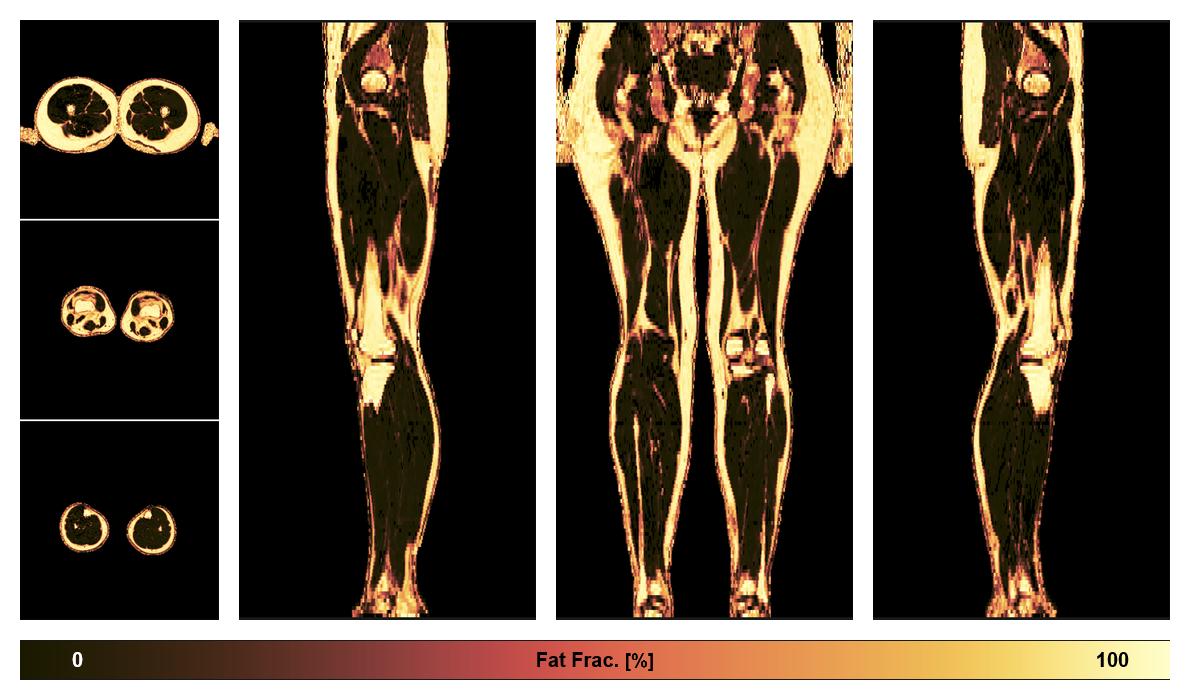

• Fat fraction

The fat fraction of the lower extremity obtained from the dixon reconstruction for muscle water fat quantification.